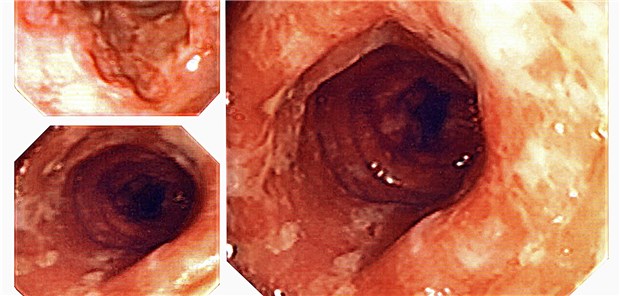

Welcher Patient mit CED eine intensive Therapie benötigt und wer nicht, kann mit Hilfe von Indices und Scores ermittelt werden. Damit lassen sich komplizierte Verläufe vorhersehen.

Die Colitis ulcerosa gehört zu den chronisch-entzündlichen Darmerkrankungen. Anamnese und körperliche Untersuchung werden bei Kassenpatienten über die Versichertenpauschale abgerechnet.